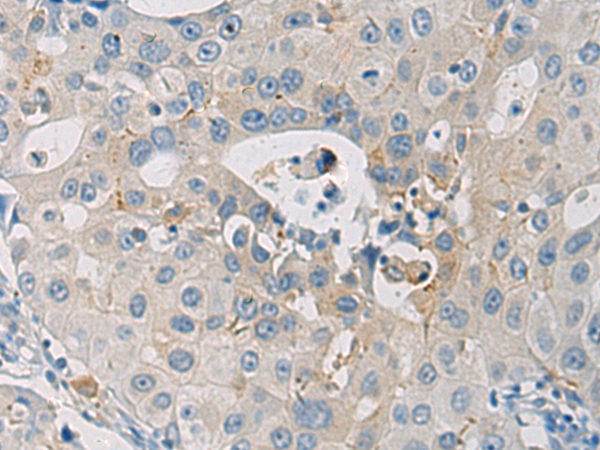

分类: 科研抗体货号: P12878别名: OOMD5; WEE1B应用: IHC反应种属: Human